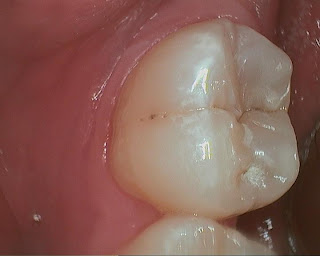

This tooth was diagnosed for occlusal composite over a year ago. Pt did not set appointment when I reminded him again that there is a large decay. He used demand force review system to question if the diagnosis was correct, because he had never had any symptoms, nor had been advised of so many filling before I took over previous owner's practice. BTW, demand force review system is a great way to get feedback from patients, there are a lot of information that they may feel uncomfortable sharing with you face to face. There is clearly a large radiolucency under the thick layer of occlusal enamel.  The pre-op intra-oral photo does not show large decay, only deep grooves with a shadow coming through enamel.

I replied to him and promised that I can show him photos of the tooth while we are working on it, step-by-step. He came in for filling on #18. Here is a sequence of photos taken with caries detector: